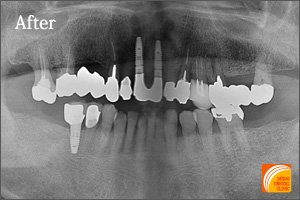

症例4

Before

期間 :5カ月

回数 :6回

費用 :1,155,600円

内容 :インプラント3本、GBR、セラミック冠3本分含む

After

上の歯1本、下の歯2本インプラントを埋入した患者さんです。患者さんのご希望通り、前後の歯を削って歯に負担をかけるブリッジや、違和感があり、こまめな清掃が必要な部分入れ歯を回避できます。